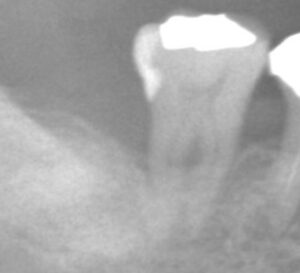

手術直後のレントゲン写真です。

歯石は取れていますが、もちろん骨は溶けたままで凹んでいます。

半年後のレントゲン写真をお見せします。

いかがでしょうか。

骨が元の位置まで戻っているとは言えませんが、

凹んでいた部分はなくなっています。

つまり、骨は一部再生したのです。

もう一度、治療の前後で比較してみましょう。

治療前

治療後

骨が再生しているのがわかります。

ただし、健全な状態まで骨が回復したとは言えません。

歯の長さの半分くらいまでしか骨がないので、

歯周病により骨が吸収してしまった状態であることは変わっていません。

ですが、治療前と比べて、

局所的に骨が溶けている部分はなくなり、

骨のラインがなだらかに、そしてはっきり見えるようになっています。